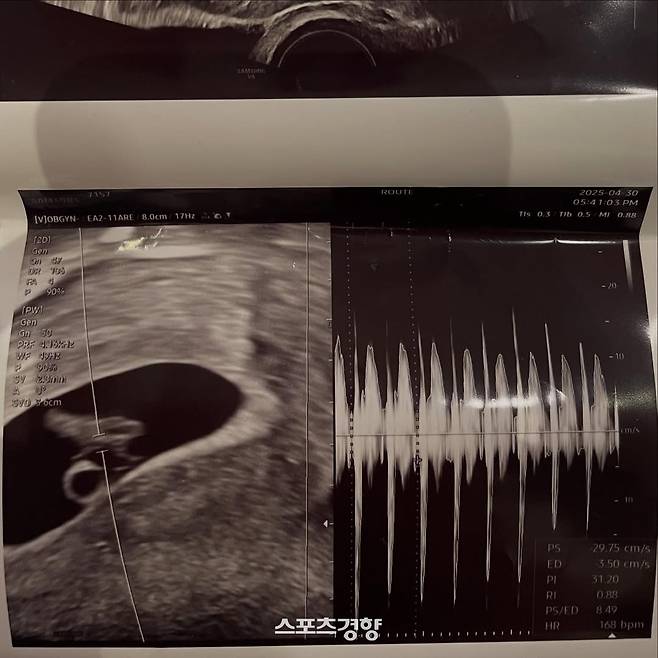

이와 함께 서민재는 자신의 연인과 함께 찍은 사진을 올리며 초음파 사진도 공개했다. 자신과 연인 사이에 아이가 생긴 것을 대중에게 알린 것이다. 이뿐 아니라 연인과 함께 찍은 다수의 사진을 함께 첨부했다.